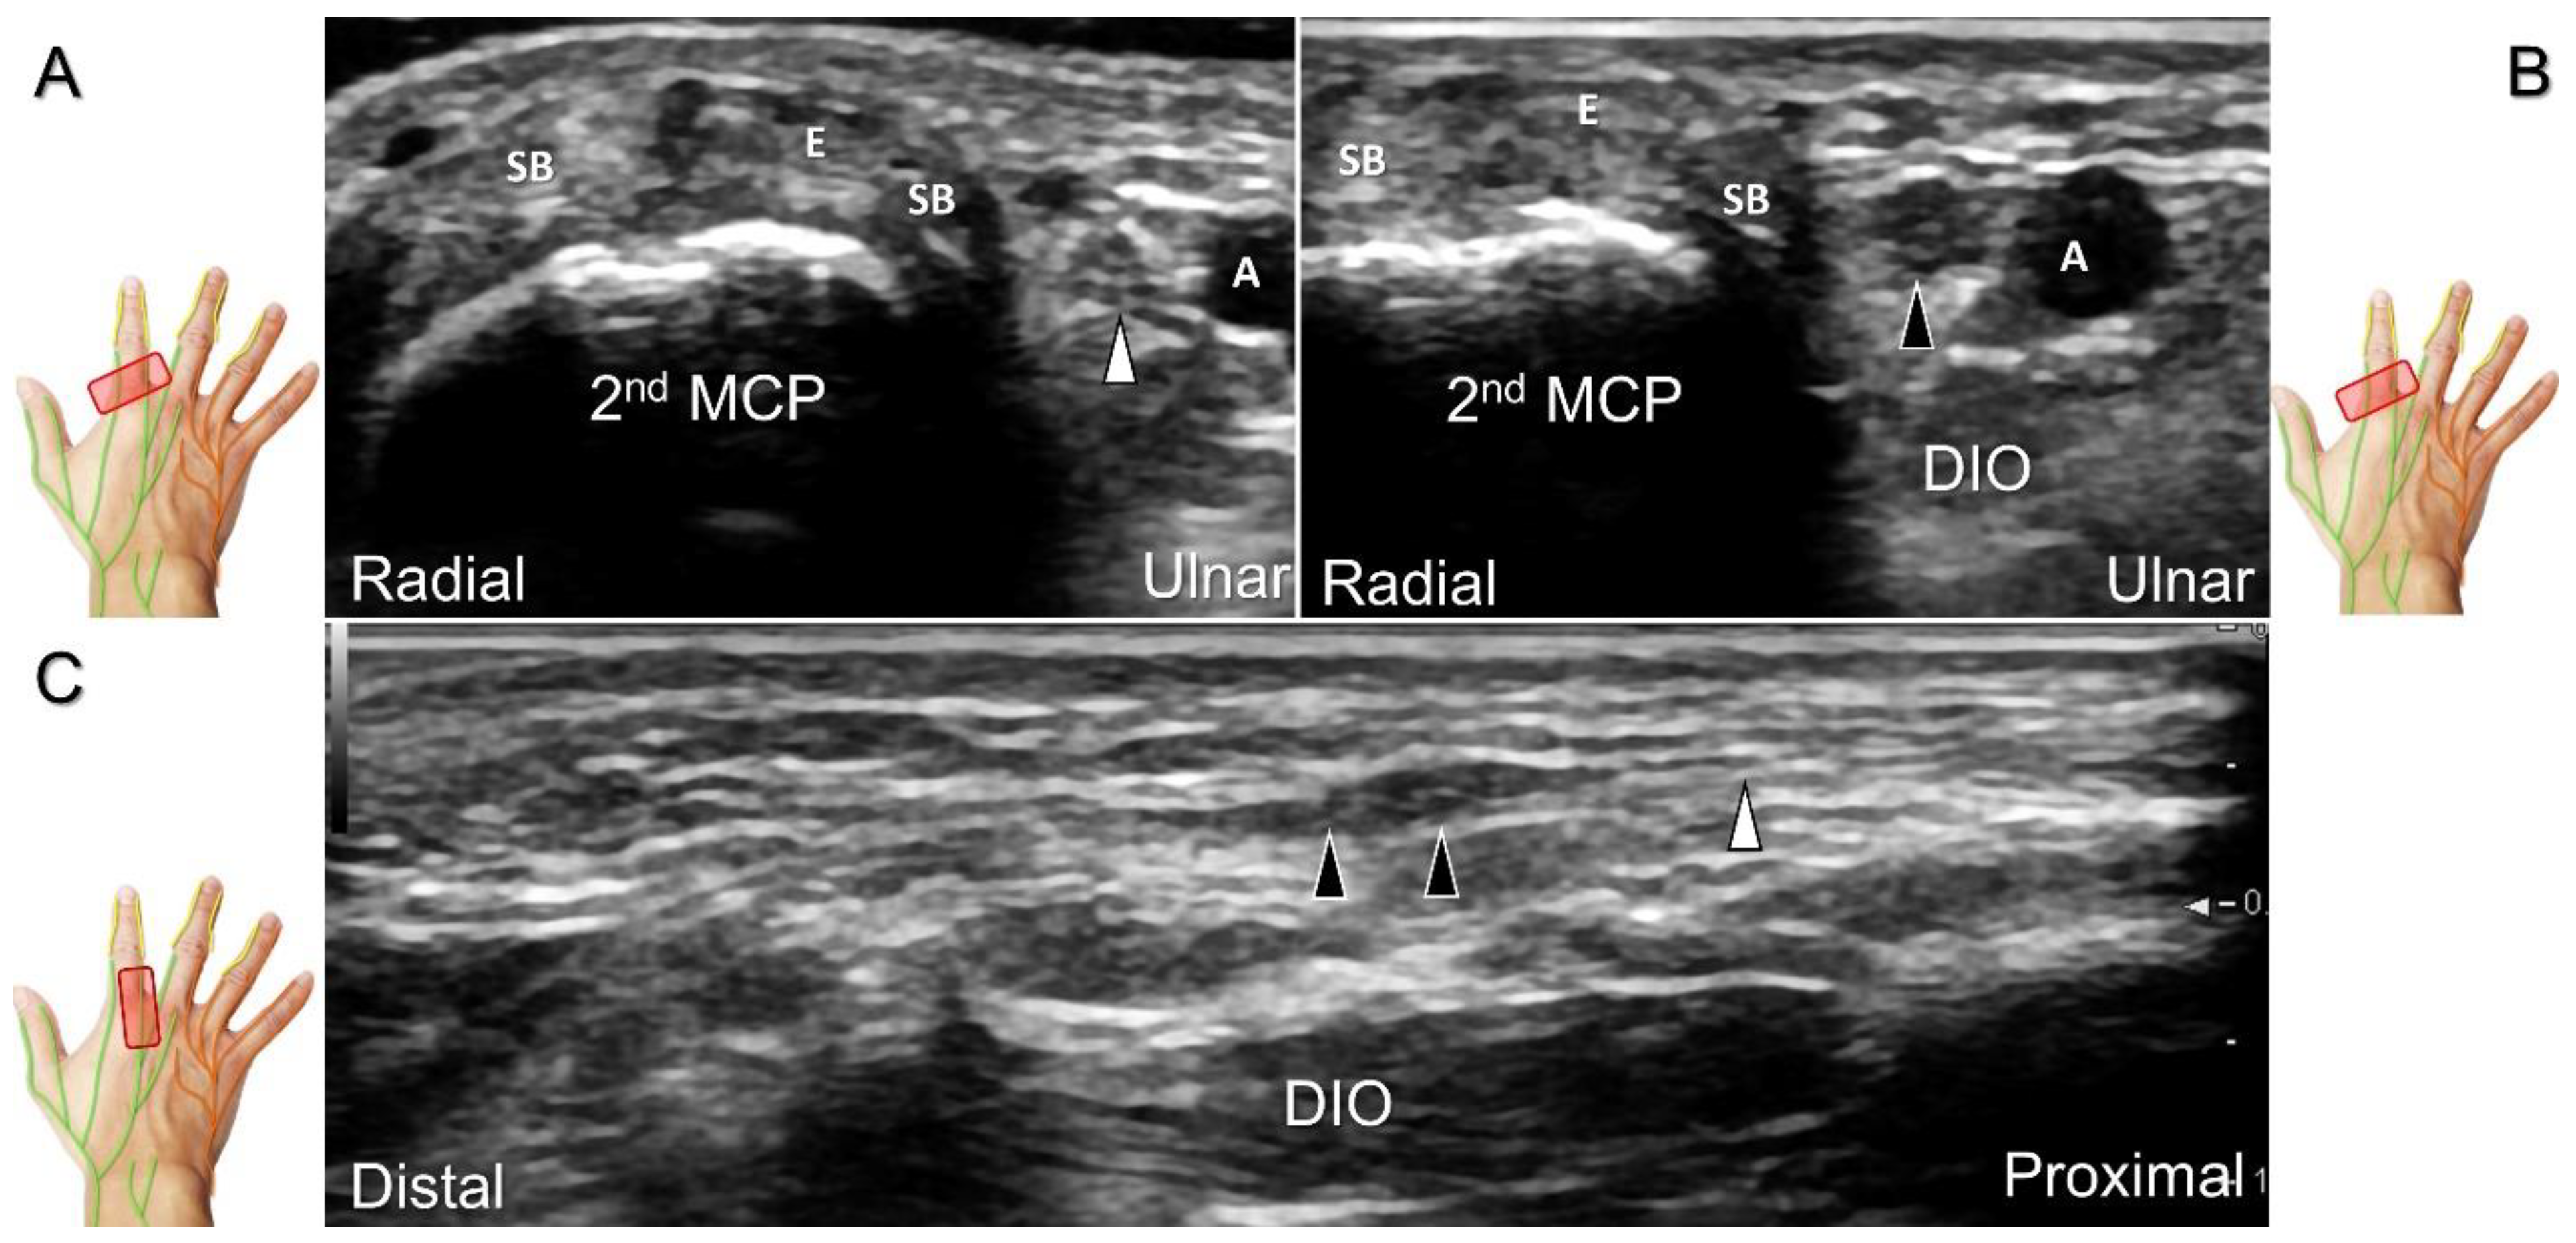

Scanning Technique

The transducer is positioned on the axial plane of the dorsal metacarpal joint in the target digit. The dorsal proper digital nerves can be found on either side of the sagittal band (Figure 33A). The transducer is moved proximally and the dorsal common digital nerves can be observed superficial to the extensor (usually the extensor digitorum proprius) tendons (Figure 33B). By returning to the level of the sagittal band and moving the transducer distally, the dorsal proper digital nerves can be seen superficial to and alongside the central slip of the finger extensor tendon (Figure 33C). Alternatively, moving the transducer distally toward the proximal phalanx of the first to the radial aspect of the fourth phalanx allows observation of the nerve fascicles of the palmar proper digital nerve originating from the median nerve (Figure 33D).

Figure 33. Sonographic imaging of the dorsal common digital nerve on the metacarpal bone (A), toward the metacarpal head (B). Dorsal proper digital nerves on the proximal phalanx (C), and the terminal nerve originating from the palmar proper digital nerve on the distal phalanx of third finger (D). Arrowheads: dorsal common digital nerve; arrows: palmar proper digital nerve. MCP: metacarpal bone; SB: sagittal band; E: extensor tendon; Cs: central slip; PP: proximal phalanx; T: terminal band; DP: distal phalanx; DIO, dorsal interosseous muscle.